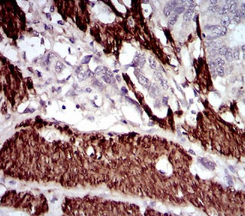

| AC1972 | CNN1 Mouse Monoclonal antibody[1H5B5] | 100ug | $367 | 10days |

| AC1972 | CNN1 Mouse Monoclonal antibody[1H5B5] | 200ug | $660.6 | 10days |